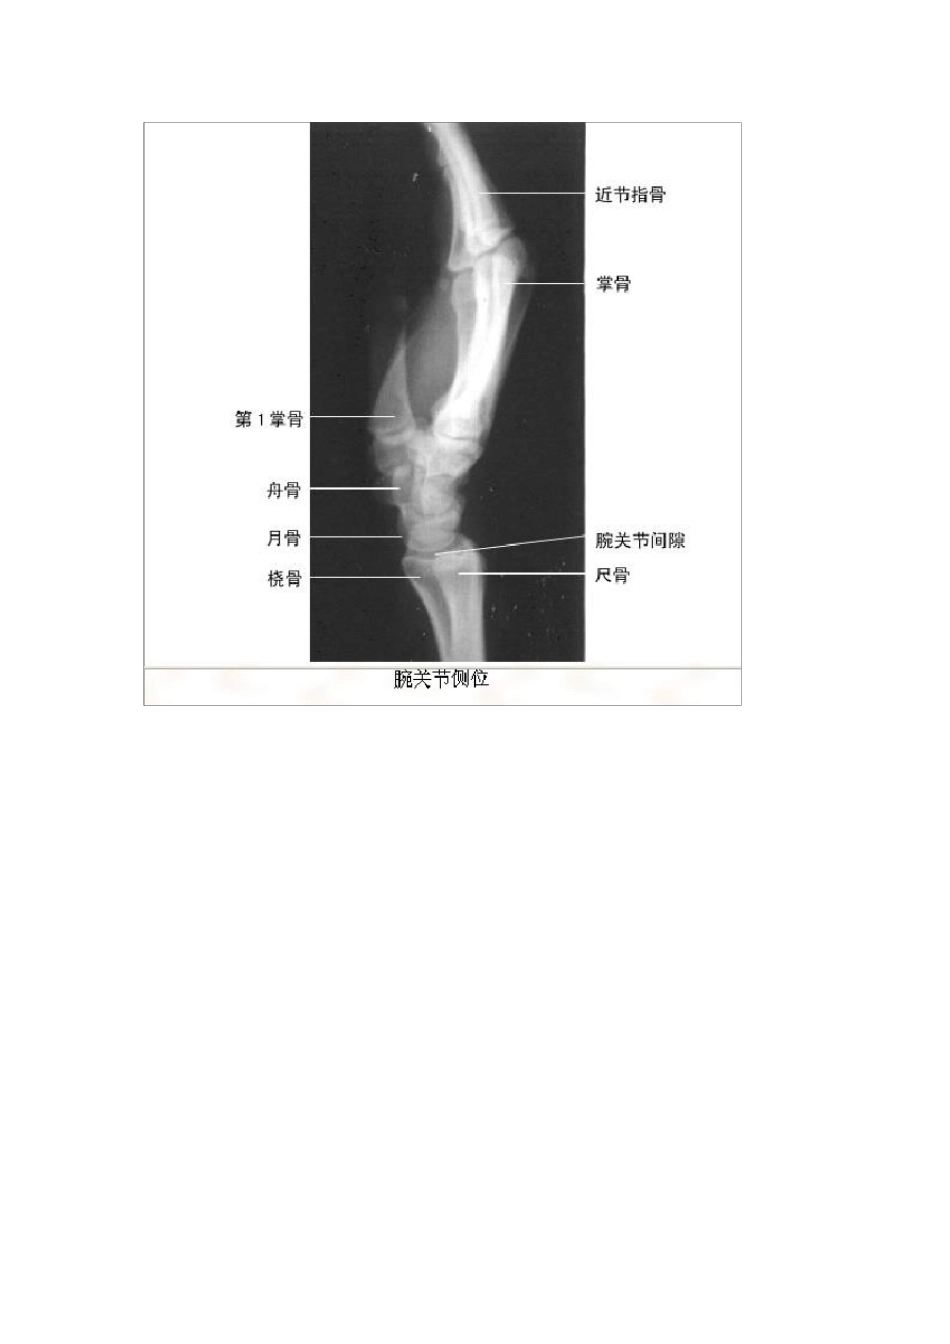

最全影像解剖影像图谱珍藏版